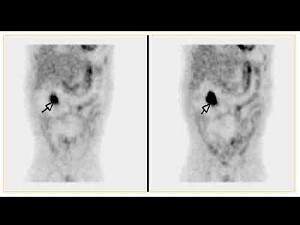

F-FDG显像如图,诊断是()

A.肝转移

B.结肠癌复发

C.腹主动脉旁淋巴结转移

D.结肠癌复发并肝转移

E.以上都不是